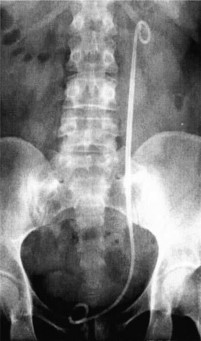

Hình 1.11. Đầu dưới ống thông JJ không cuộn tròn hết

(Nguồn: El-Nahas A.R., 2006) [51]

Theo Rabe A. và cs (2001) [151] nghiên cứu 60 trường hợp mang ống thông niệu quản JJ trong một tuần liên quan đến than phiền về các triệu chứng của đường tiết niệu dưới. Qua phân tích kết quả nghiên cứu, các trường hợp có đầu dưới ống thông niệu quản vượt đường giữa bàng quang qua bên đối diện hoặc không cuộn tròn hết trong bàng quang (Hình 1.11) là nguyên nhân gây ra các triệu chứng đường tiểu dưới là tiểu gấp (57%), tiểu nhiều lần (47%), đau (30%), tiểu máu (25%).